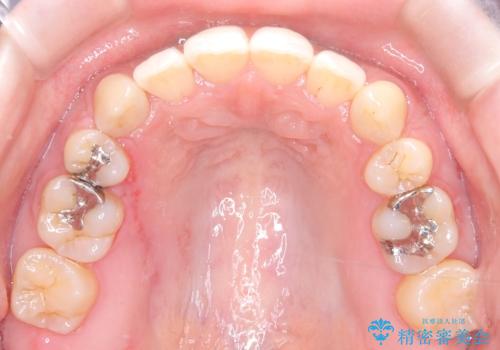

- 前歯のガタガタや八重歯の位置の乱れが気になっていた患者様に対して、ワイヤー矯正を行いました。矯正の過程で、スペースを確保するために上下左右の小臼歯を抜歯し、歯全体のバランスと機能性を考慮しながら理想的な歯列に仕上げました。

治療後は、前歯の位置や噛み合わせが整い、見た目も機能面も大きく改善されました。きれいな歯並びを得ることができ、患者様にも非常に満足していただけました。

抜歯によって確保したスペースを活用し、効率的に歯列を整えました。前歯のガタガタと八重歯が解消され、自然で美しい仕上がりを実現しました。